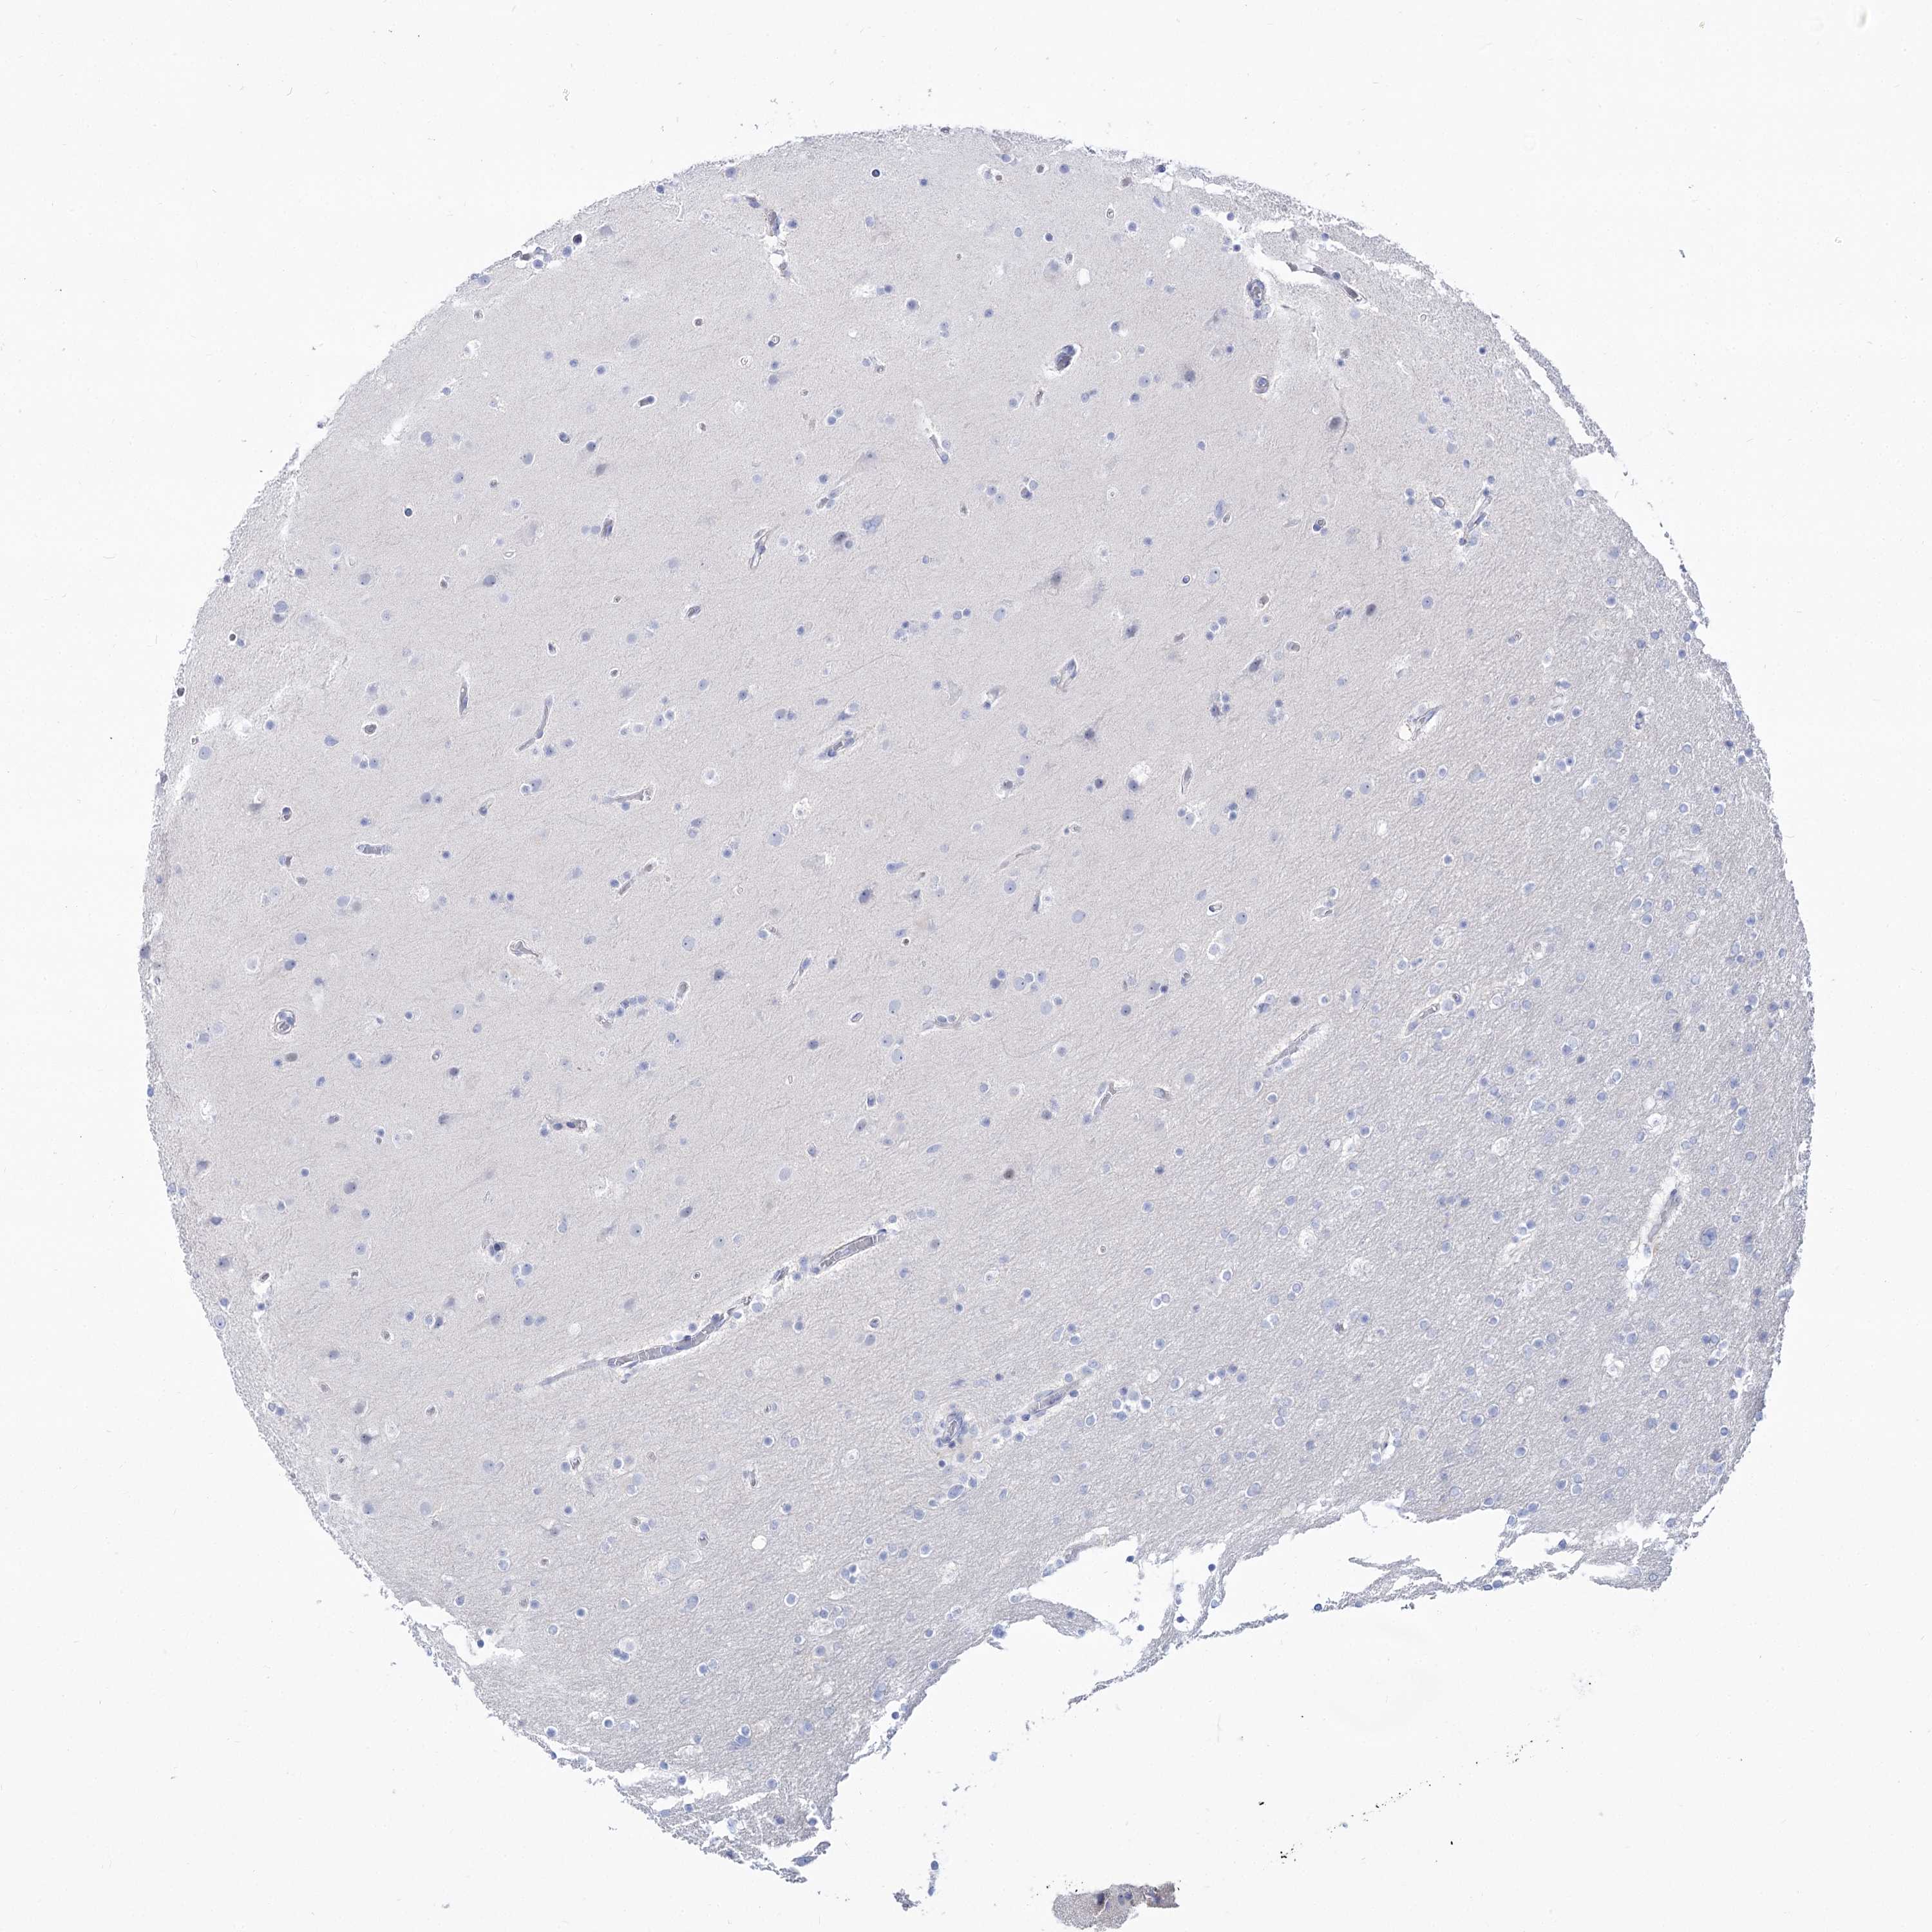

GLIOMA - Protein expressioni

A mouse-over function shows sample information and annotation data. Click on an image to view it in a full screen mode. Samples can be filtered based on level of antibody staining by selecting one or several of the following categories: high, medium, low and not detected. The assay and annotation is described here.

Note that samples used for immunohistochemistry by the Human Protein Atlas do not correspond to samples in the TCGA dataset.

Antibody stainingi

Antibody staining in the annotated cell types in the current human tissue is reported as not detected, low, medium, or high, based on conventional immunohistochemistry profiling in selected tissues. This score is based on the combination of the staining intensity and fraction of stained cells.

Each image is clickable and will lead to virtual microscopy that enables deeper exploration of all samples and also displays staining intensity scores, fraction scores and subcellular localization as well as patient and tissue information for each sample.

Antibody HPA038208

Antibody HPA038209

Staining

High

Medium

Low

Not detected

Intensity

Strong

Moderate

Weak

Negative

Quantity

>75%

75%-25%

<25%

None

Location

Nuclear

Cytoplasmic/membranous

Cytoplasmic/membranous,nuclear

Glioma, malignant, High grade

Glioma, malignant, Low grade

Glioblastoma, NOS